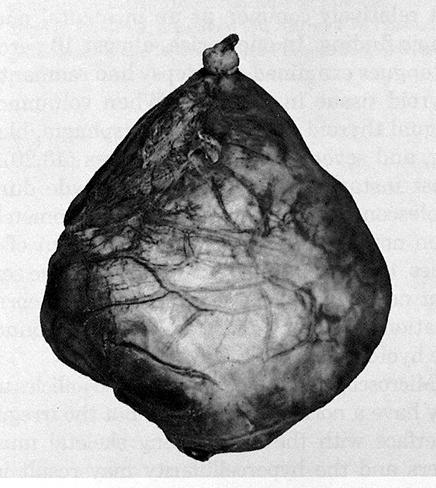

Gross description

- The thyroglossal duct is a continuous tract from the base of tongue, but occasionally is multiple and aborizing, with a dominant cyst and smaller cysts that are identified microscopically (J Pediatr Surg 1984;19:506, J Pediatr Surg 1991;26:766)

- Cysts are unilocular or multilocular with rounded, smooth external surfaces

- Cyst has a mean diameter of 2 cm, range 0.2 - 7 cm (J Am Coll Surg 2002;194:274, Endocr Pathol 2015;26:75), giant cysts >10 cm are also described (Ann Surg 1954;139:123)

- Cystic content includes clear mucinous or viscous fluid / gel having a broad range of color (clear, yellowish tan, reddish brown and grayish white) and degree of opacity; infected cysts contain purulent exudate